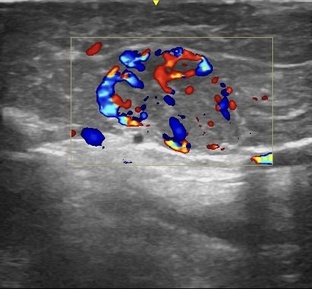

Работа хирурга требует высокой квалификации, опыта и насмотренности. Иногда кажется, что на снимке всё очевидно и различимо невооружённым глазом, но в реальности диагностика и тактика лечения – куда сложнее, чем может показаться. Каждый нюанс имеет значение, и правильное решение требует не только технических навыков, но и глубокого понимания процессов, происходящих в организме. 🩺 Изображение 1 – на УЗИ визуализируется изогипоэхогенная опухоль в толще поджелудочной железы. Контуры четкие, размеры около 2×1,5 см...